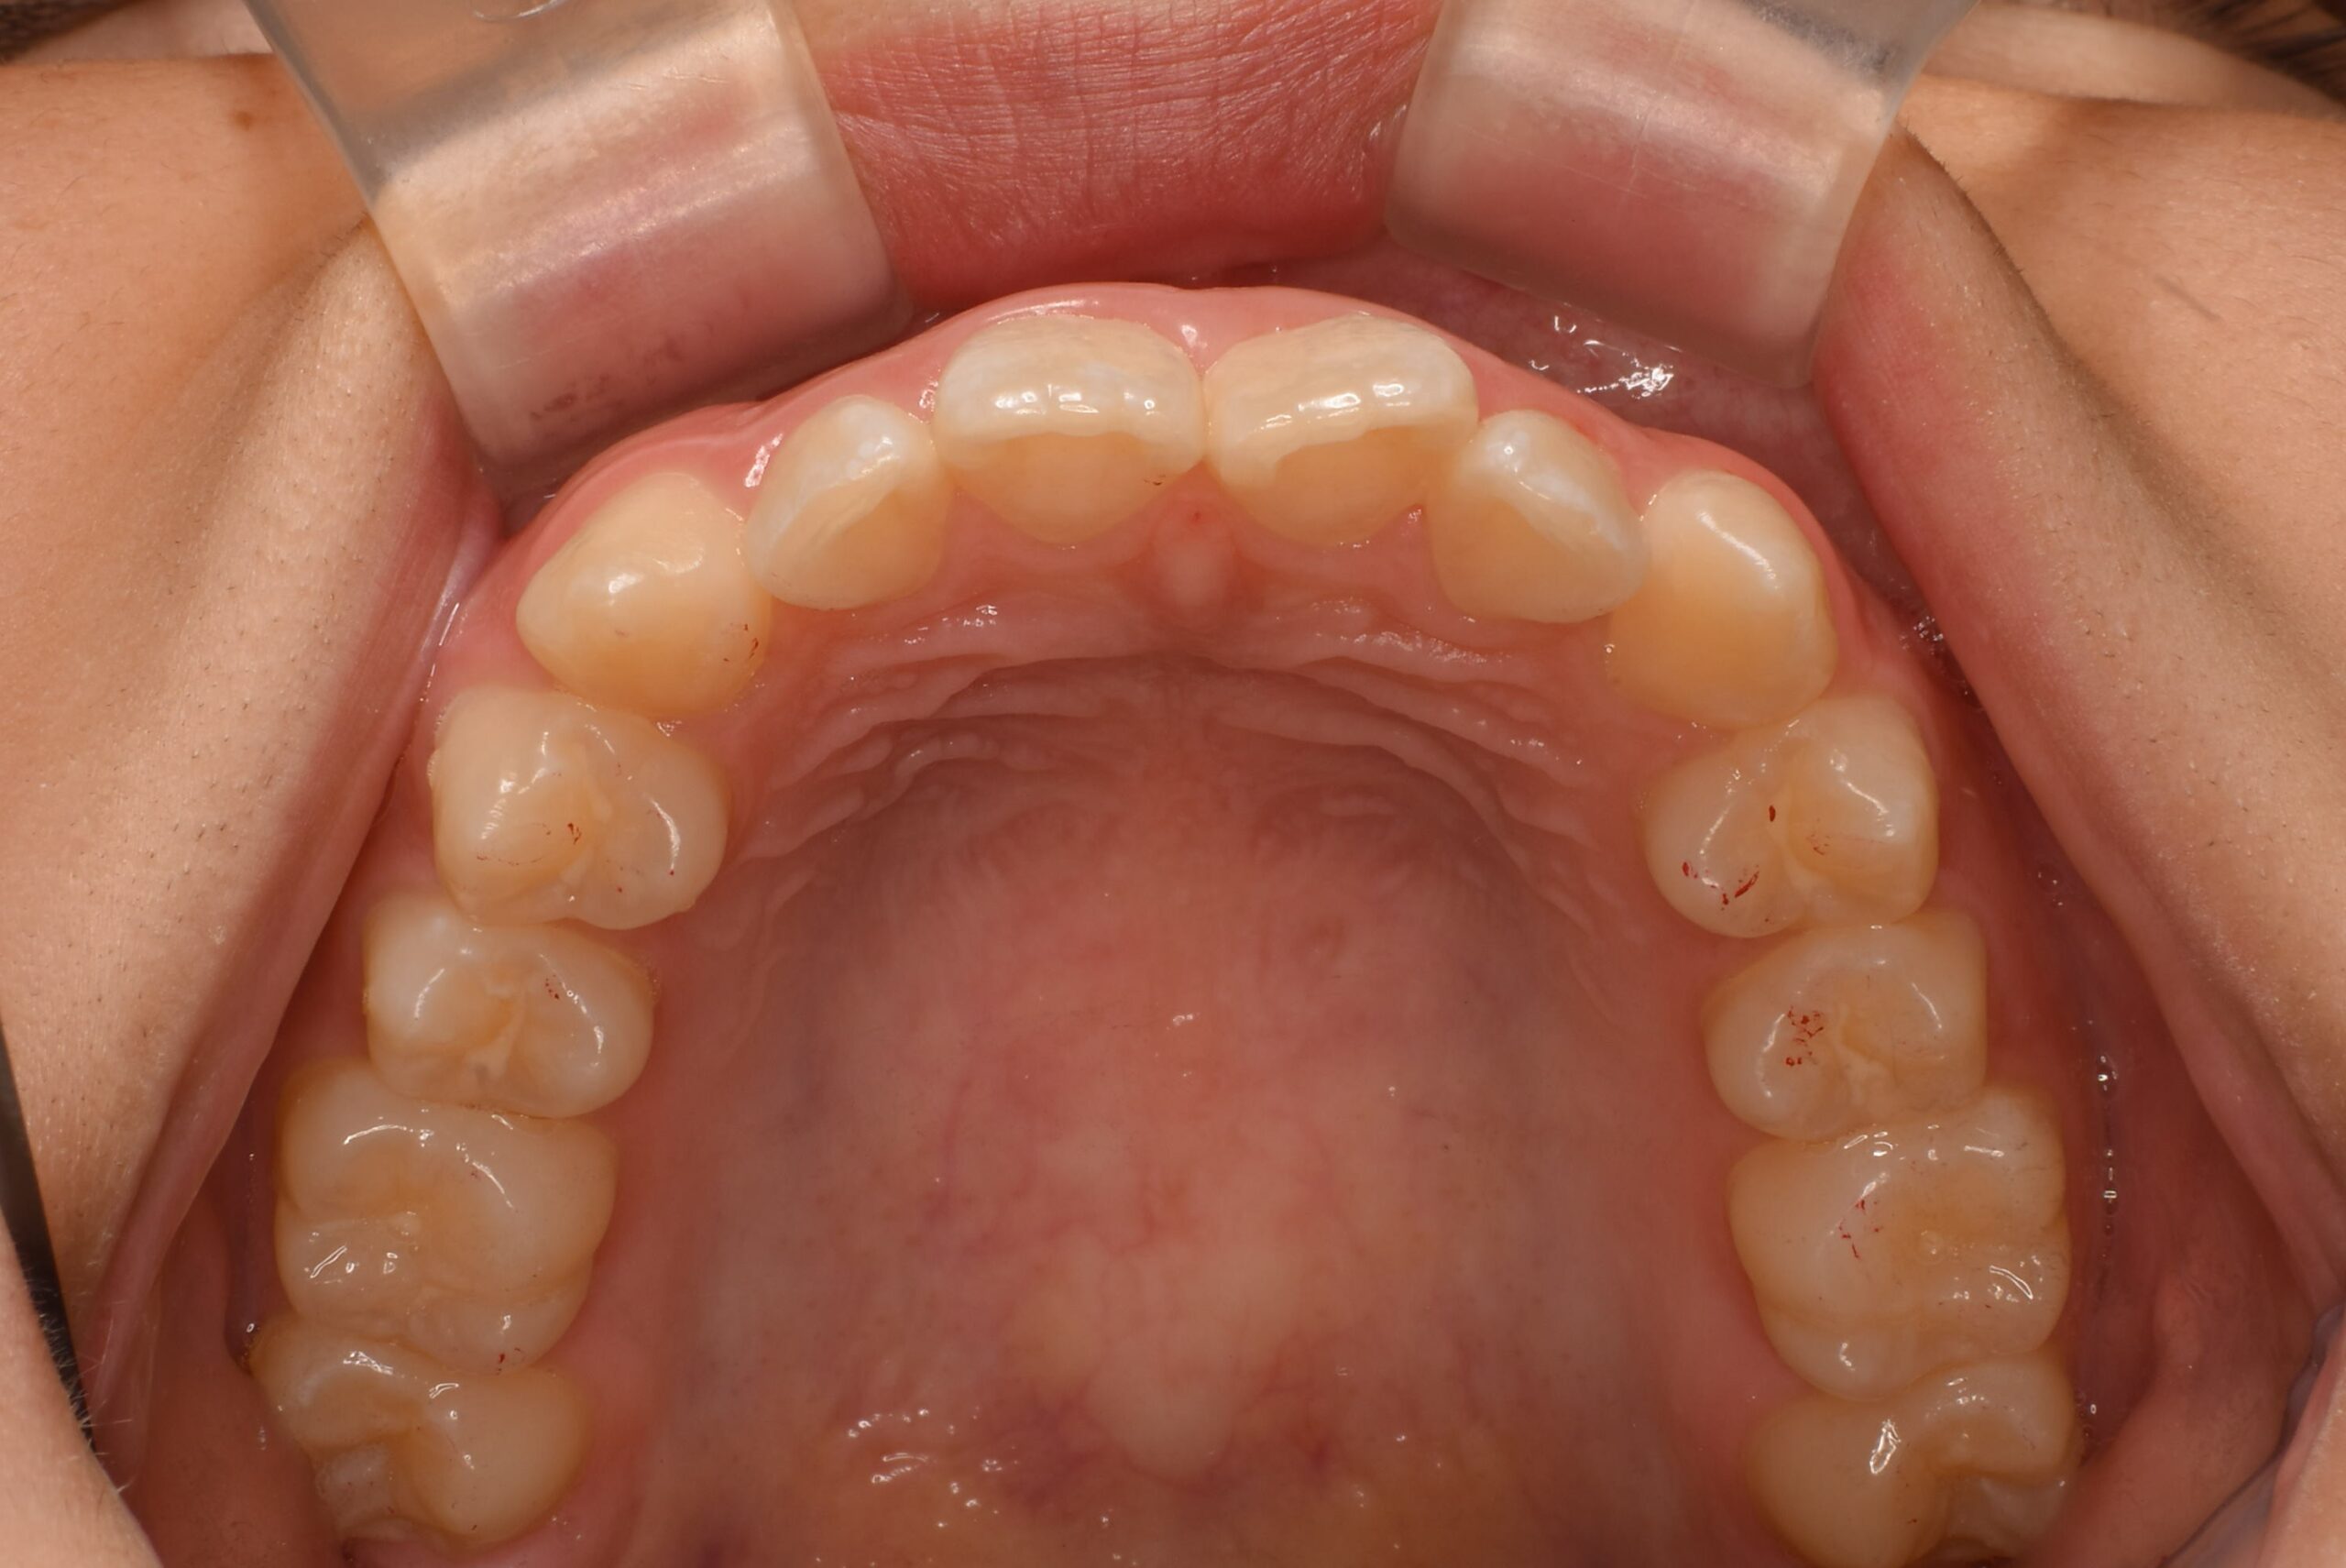

• 治療前_上顎咬合面